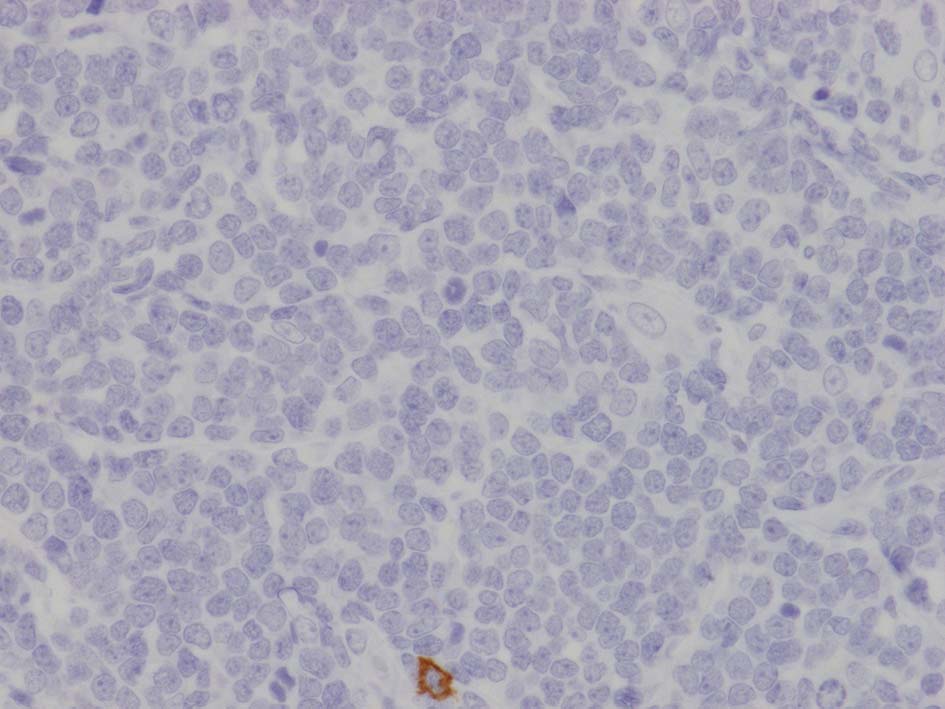

FCMでTdT陽性細胞が多数. 免疫染色ではCD3+, CD4+, CD8+, BCL2+. TdT+, CD99(MIC2)+, CD34-, CD117(c-KIT)-であった.

左肘窩リンパ節の病理診断は T-lymphoblastic lymphoma(T-LBL)になる. 1年後の再発で, 精巣リンパ腫と異なったものが発症するとは考えにくく, 精巣病変にTdT, CD99, CD34, CD117を追加染色した.